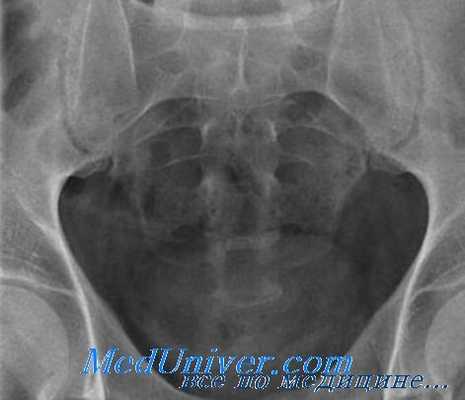

Определяющим моментом в диагностике повреждений крестца является рентгенография в двух проекциях. Однако более чем в половине случаев с подозрением на перелом крестца требуется дополнительное рентгенологическое обследование. Эти сведения дают томограммы во фронтальной и сагиттальной проекциях, рентгенограммы в косых проекциях, а также рентгенограммы в прямой проекции при наклоне трубки кзади на 40-50°. В особо сложных случаях диагноз устанавливают с помощью КТ. Учитывая преимущественно множественный характер повреждений крестца, прямая проекция должна включать все кости таза, IV и V поясничные позвонки, а боковая - нижнепоясничные позвонки, копчик.

Переломы крестца могут быть как горизонтальными, так и вертикальными. Вертикальные переломы являются следствием воздействия непрямого механизма и обычно пересекают тазовое кольцо. Вертикальные переломы крестца будут рассмотрены в разделе о повреждениях класса Б, поскольку они относятся к повреждениям, нарушающим непрерывность тазового кольца. Ниже обсуждаются только горизонтальные переломы крестца.

Перелом таза. Перелом крестца. А — горизонтальный, Б — вертикальный

Поперечные переломы крестца не всегда легко различить на обзорных рентгенограммах таза. Поперечные переломы имеют тенденцию возникать дистальнее крестцово-подвздошного сочленения. Неправильная форма или прогиб межпозвонкового отверстия указывают на перелом крестца со смещением.

Часто для выявления переломов крестца со смещением лучшими оказываются снимки в боковой проекции или прямой проекции с наклоном стола в головную сторону.